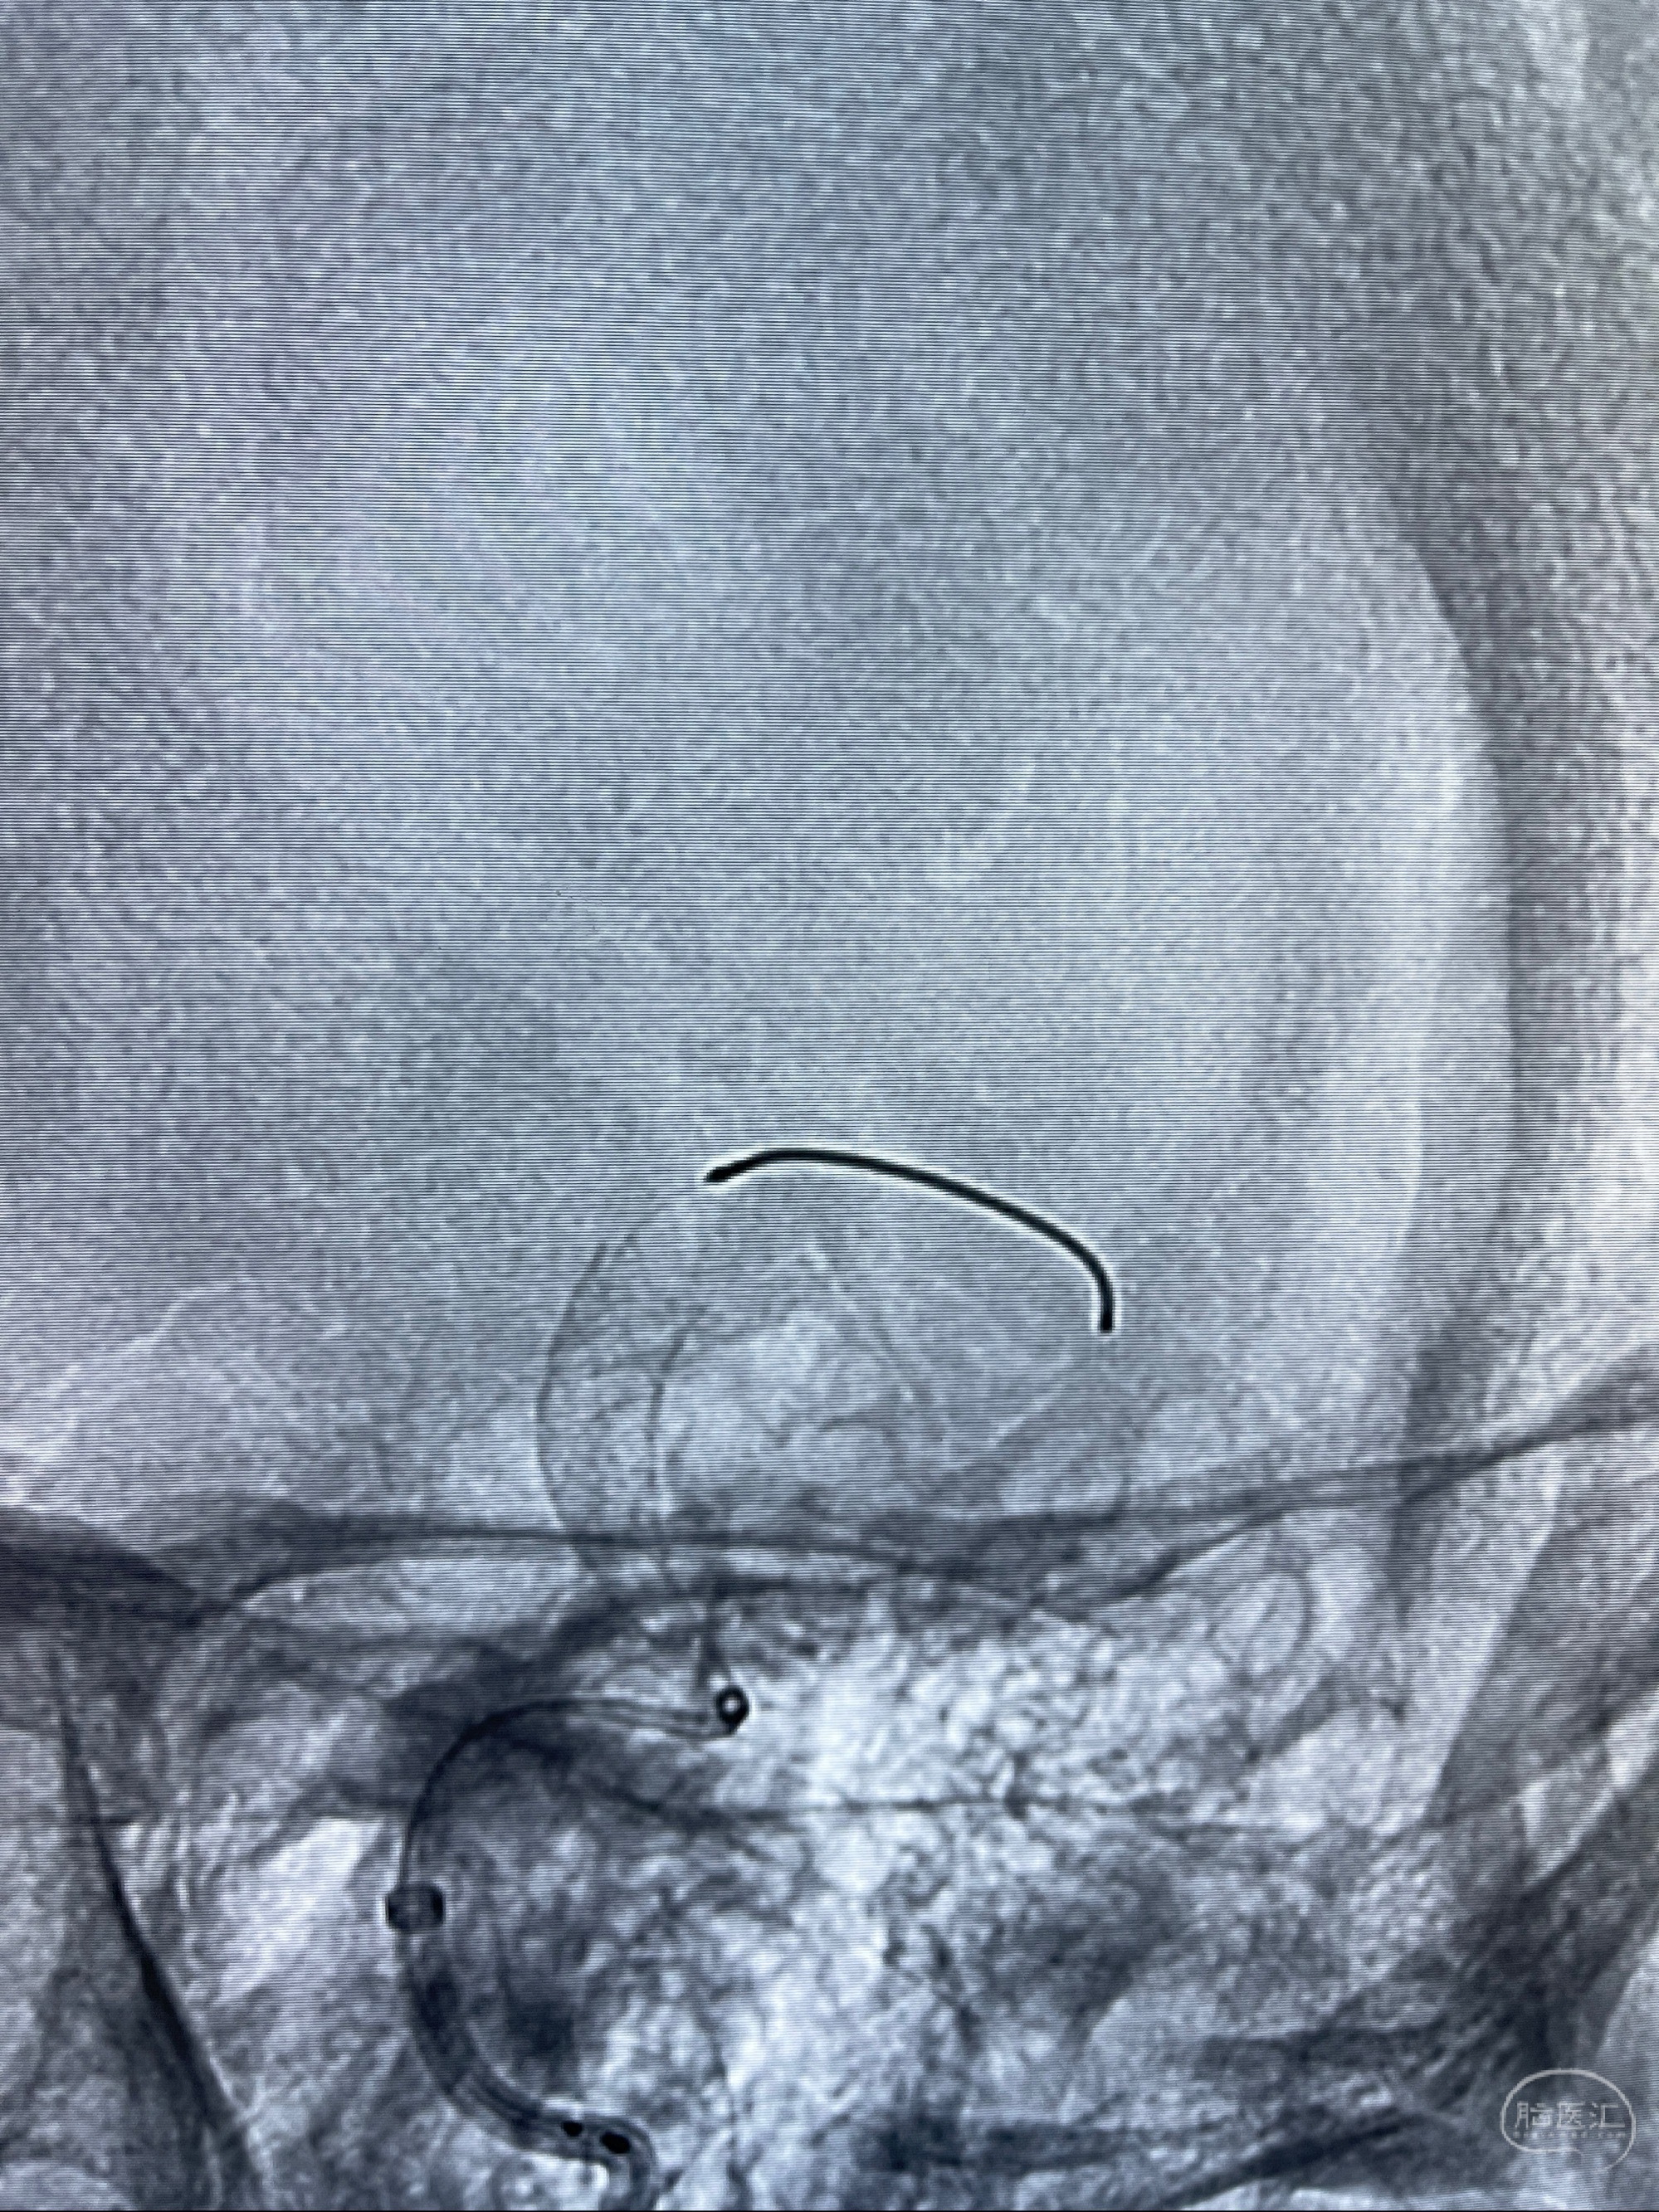

2023-07-27全脑血管造影:双侧颈内动脉眼动脉段动脉瘤,右侧较大

2023-08-01全麻下行双侧颈眼动脉瘤支架辅助栓塞

- pipeling4.5-20mm

- pipeline 4.0-20mm